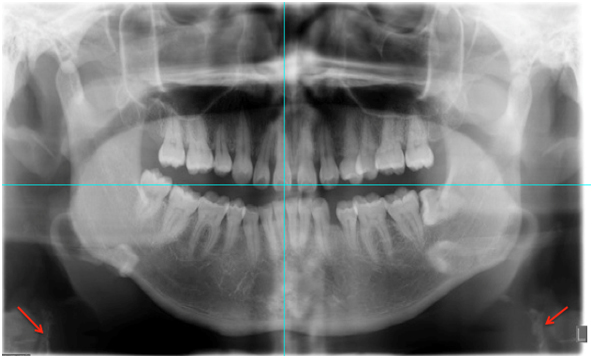

In the seven orthopantomographies with carotid calcifications, 57.1% (4) were bilateral and (42.9%) 3 unilateral (Table 1) (Figure 1).

Figure 1. Patient 1-7